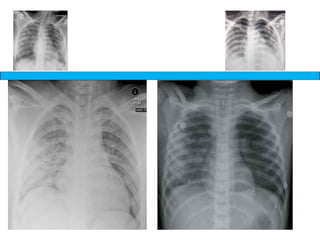

A medical document discusses hypoxia following a road traffic accident. It describes four types of pulmonary contusion caused by direct chest compression, shearing against vertebral bodies, fractured ribs directly injuring the lung, or tearing of lung parenchyma due to prior adhesions. The document also mentions management of pulmonary contusion.